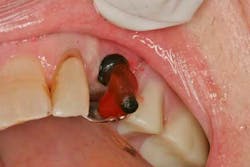

The RPD was fully seated and the plastic parallel posts were bonded to the RPD using GC Pattern Resin (GC America) (figure 3). This is done to ensure a very accurate and stable fit of the parallel posts, which are being used as impression transfers in this case.